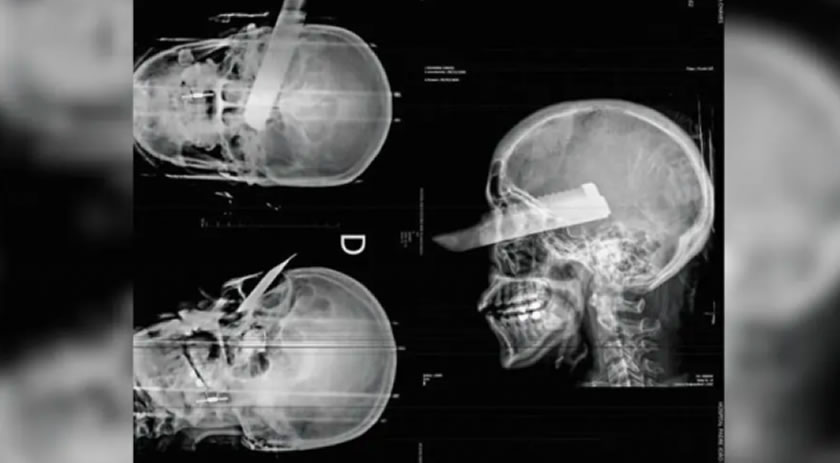

Uma mulher sofreu uma tentativa de feminicídio na manhã desta segunda-feira (2) em São Carlos, no Oeste de Santa Catarina, ao ser atacada pelo companheiro dentro da residência do casal. O agressor desferiu um golpe de faca no rosto da vítima, atingindo o olho direito, mas o crime não se consumou, segundo a polícia, graças ao pronto atendimento médico.